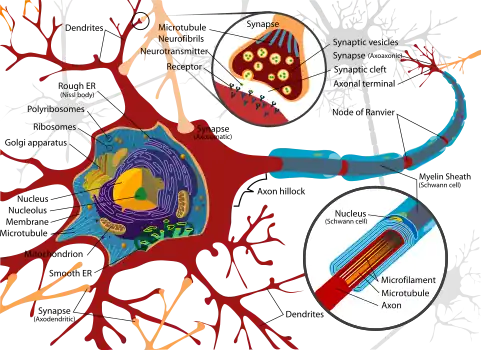

Medicine has been practiced since prehistoric times, and for most of this time it was an art (an area of creativity and skill), frequently having connections to the religious and philosophical beliefs of local culture. For example, a medicine man would apply herbs and say prayers for healing, or an ancient philosopher and physician would apply bloodletting according to the theories of humorism. In recent centuries, since the advent of modern science, most medicine has become a combination of art and science (both basic and applied, under the umbrella of medical science). For example, while stitching technique for sutures is an art learned through practice, knowledge of what happens at the cellular and molecular level in the tissues being stitched arises through science.